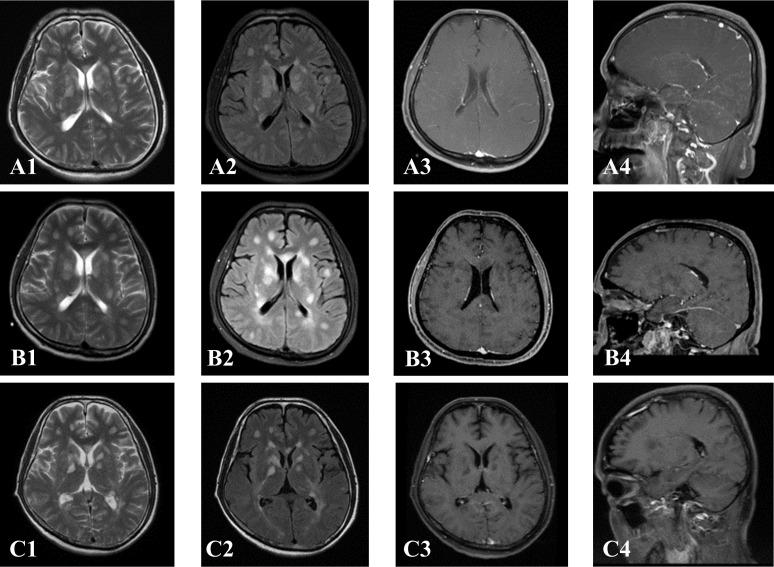

The predominant GFAP-A clinical manifestations are limb weakness/numbness and fever. GFAP-A has a propensity in the early stage for meningeal and leptomeningeal lesions on the brainstem surface, with a typical pattern of periventricular linear radial and leptomeningeal enhancement. The clinical manifestations and leptomeningeal enhancement were rapidly alleviated after treatment with high doses of corticosteroids or/and intravenous immunoglobulin, although, there are patients who may present with increased brain parenchymal lesions. On 3T MRI, the spinal cord demonstrated extensive longitudinal T2-weighted hyper-intensity, central distribution, and gray matter involvement. Optic nerve involvement in some patients was also noted with optic nerve swelling and abnormal enhancement. In addition to the classic reversible splenium of corpus callosum syndrome (type I), this study found the much rarer type II with diffusion restriction on DWI (Diffusion Weighted Imaging) in the corpus callosum. Positive anti-GFAP antibodies in serum or cerebrospinal fluid (CSF) are important for GFAP-A diagnosis with overlapping antibodies commonly noted. This study found anti-GM3 antibodies, a rare finding also previously reported.

GFAP-A的主要临床表现为肢体无力/麻木和发热。GFAP-A在早期倾向于脑干表面的脑膜和软脑膜病变,具有典型的脑室周围线性放射状和软脑膜强化模式。高剂量皮质类固醇或/和静脉注射免疫球蛋白治疗后,临床表现和软脑膜强化迅速缓解,尽管有些患者可能出现脑实质病变增加。在3T MRI上,脊髓表现为广泛的纵向T2加权高信号、中央分布和灰质受累。部分患者还出现视神经受累,表现为视神经肿胀和异常强化。除了经典的胼胝体压部可逆综合征(I型)外,本研究还发现了胼胝体在扩散加权成像(DWI)上有扩散受限的更为罕见的II型。血清或脑脊液(CSF)中抗GFAP抗体阳性对GFAP-A诊断很重要,常见有重叠抗体。本研究发现了抗GM3抗体,这也是先前报道的罕见发现。